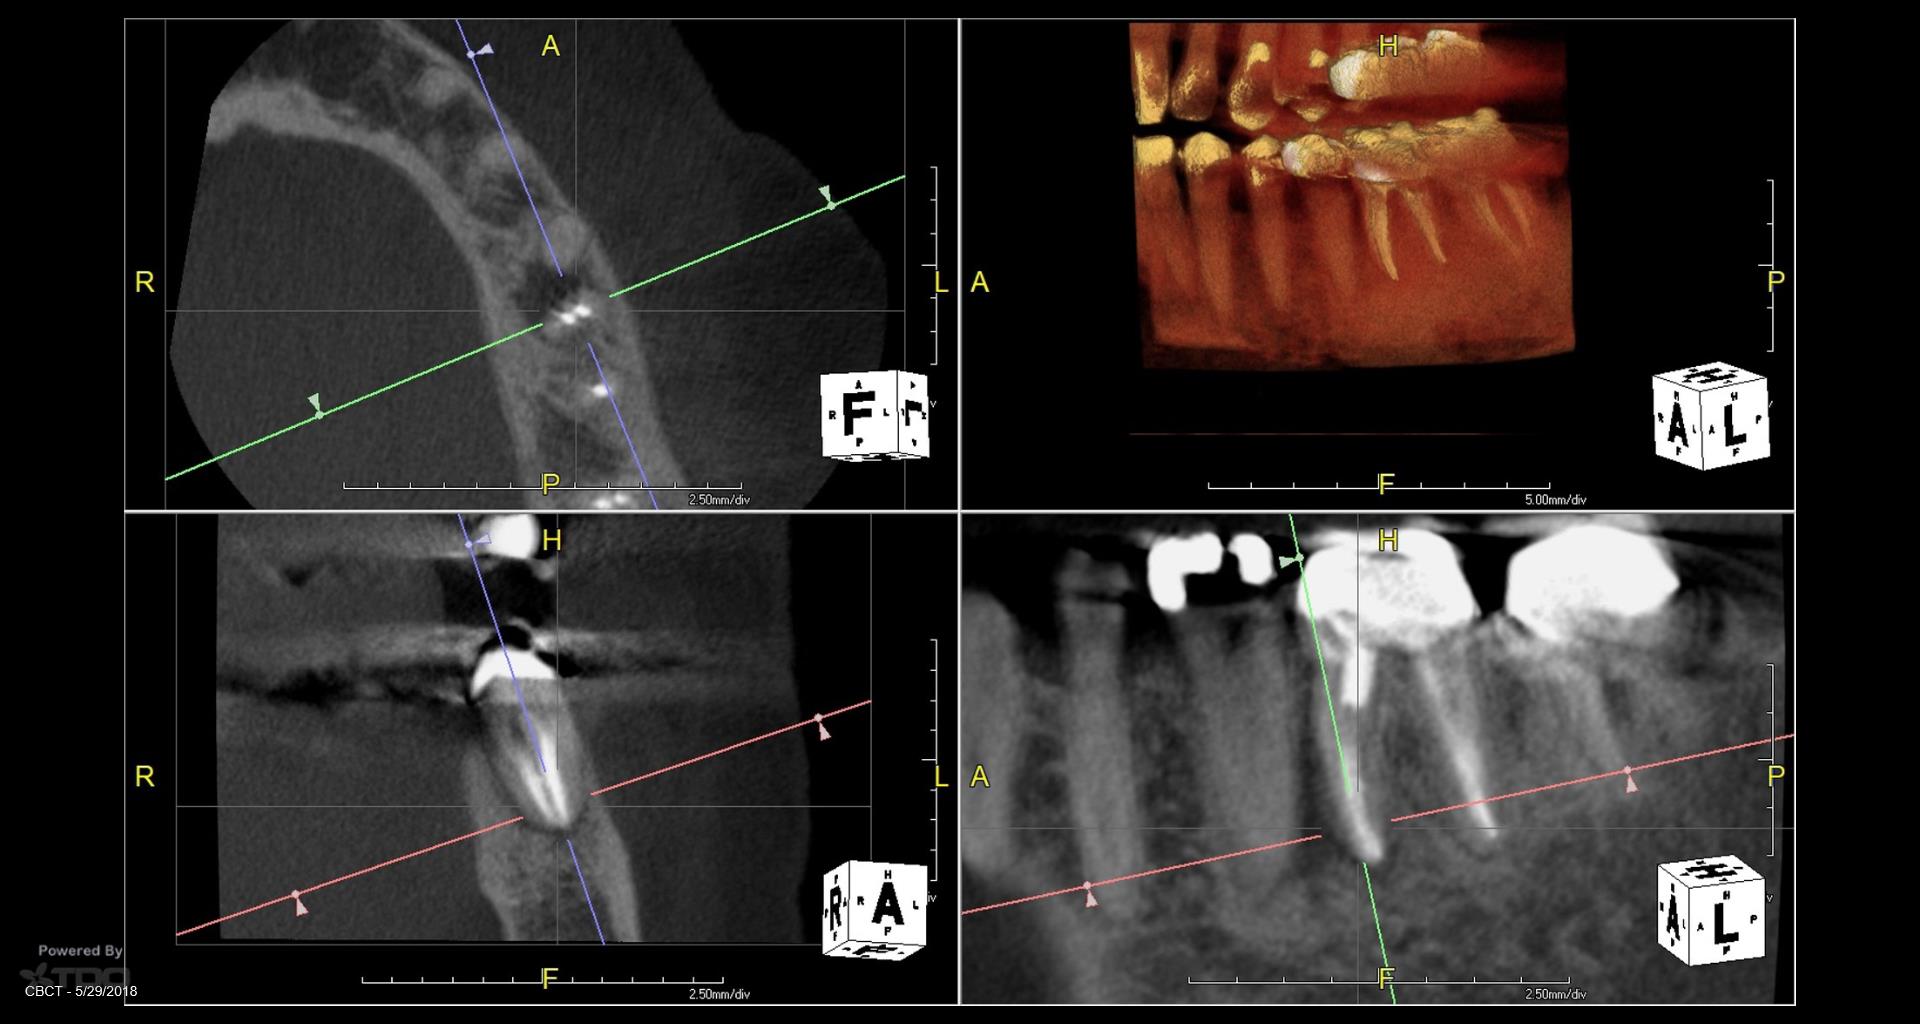

Patient in for a sinus tract check recall today asking questions…… All treatment done by endodontists. Always done in a single visit. The 2nd endodontist told the patient she was “cured”. He never checked her again. When she called and said she may have a problem… they told her it wasn’t necessary. Her GP told her to have it extracted. Is it fractured? Is it a failing RCT that can be saved? How does one tell? To me, to do a retreatment like this in a single visit….. Well…it isn’t the way I would like to be treated. Because you end up with cases like this. By the way: no symptoms. gbc